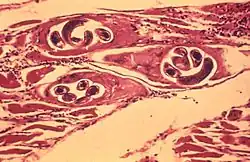

Eine Entzündung des Zwerchfells wird als Diaphragmitis bezeichnet. Sie ist eine lokalisierte Muskelentzündung (Myositis), die meist mit Zwerchfellhochstand, Schmerzen und Bewegungseinschränkung des Zwerchfells einhergeht. Eine ausschließlich auf das Zwerchfell begrenzte Muskelentzündung ist aber äußerst selten. Eine häufige Ursache war der Befall mit Trichinen (Trichinellose). Diese parasitäre Erkrankung ist durch die bei allen Schlachttieren, die keine reinen Pflanzenfresser sind, gesetzlich vorgeschriebene Trichinenuntersuchung weitestgehend zurückgedrängt. Bei der Trichinenschau wird eine Muskelprobe aus dem Lendenteil des Zwerchfells (Zwerchfellpfeiler) des Schlachttieres entnommen und mikroskopisch auf das Vorhandensein von Trichinen untersucht.